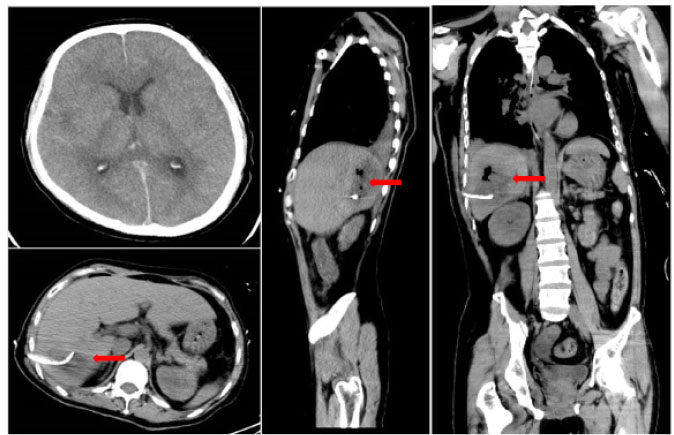

A 41-year-old male was admitted to the intensive care unit with sustained chills and fevers for 1 week and coma for 5 h. Leukocyte, neutrophil, C-reactive protein, and procalcitonin levels were high and platelet level was low. There was a significant increase in glycosylated hemoglobin, indicating undiagnosed diabetes mellitus or poor glucose control. Computed tomography (CT) revealed liver abscess with a large fluid–gas plane, but indicated no brain abnormalities (Figure 1). A diagnosis of GFPLA was made; percutaneous abscess drainage combined with anti-infective therapy was carried out, but the patient’s condition deteriorated, and bilateral pupil dilatation occurred on the next day. Immediate CT review showed brain edema and subarachnoid hemorrhage despite decrease in hepatic fluid and gas levels (Figure 2). A culture of abscess fluid and blood, along with next-generation sequencing yielded a definitive diagnosis of K. pneumoniae infection (Figures 3). Anaerobic and fungal cultures were negative. Anti-infective therapy based on drug-sensitive experiments was administered (imipenem cilastatin 2 g, every 6 hours), but the treatment was not effective and the patient eventually died of progressive cerebral swelling, herniation, and pneuomocrania (Figure 4).

Repeat CT scans on day 2 reveal emerging cerebral edema and subarachnoid hemorrhage, but there is a decrease in hepatic gas and fluid levels. Red arrowhead: after liver abscess puncture drainage, the gas in the abscess cavity had decreased obviously. CT: computed tomography.